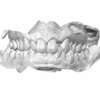

Important encombrement traité par gouttières

C-Début 3